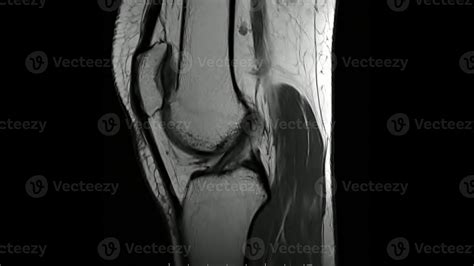

Ligaments

The knee has several important ligaments, including the anterior cruciate ligament (ACL), posterior cruciate ligament (PCL), medial collateral ligament (MCL), and lateral collateral ligament (LCL). The MRI can show tears or strains in these ligaments, which are often the result of sports injuries.

Tendons

Tendons connect muscles to bones. The MRI can detect inflammation or tears in the tendons, such as the patellar tendon, which connects the kneecap to the shinbone.

• normal knee mri sagittal